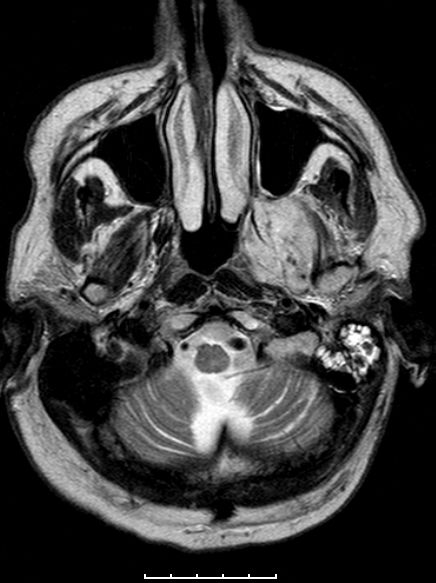

| Fall | Im vorliegenden Fall kam es während der Temodal-Therapie nach postoperativer Radiochemotherapie zu einen Durchbruch des GBs durch die Schädelbasis. | |